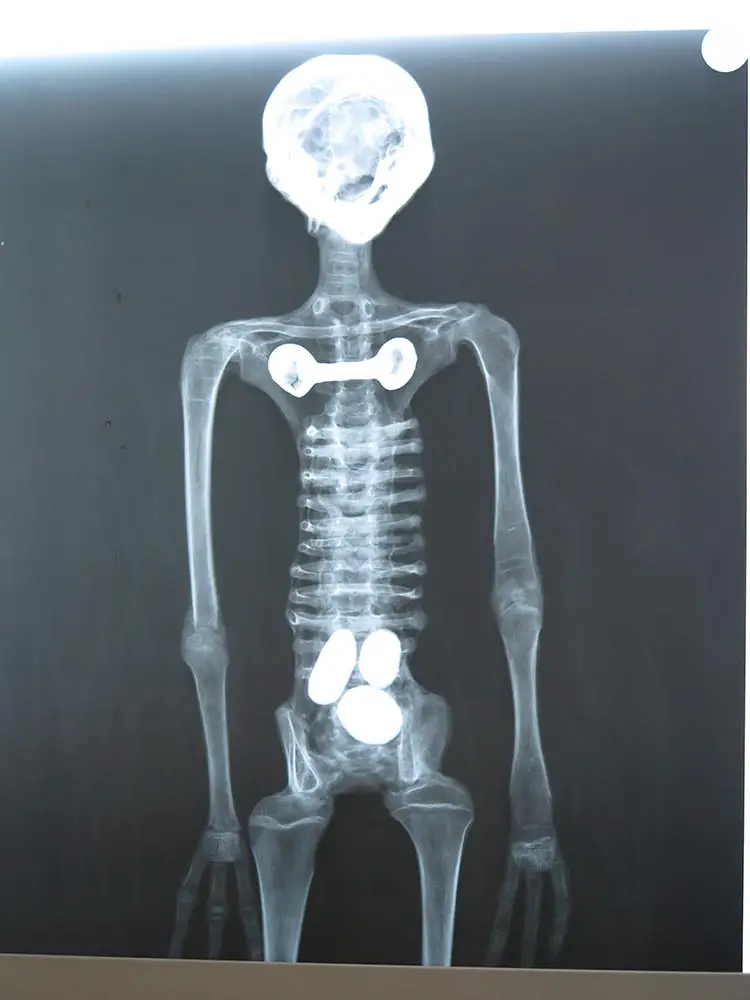

Le professeur Roger Zuniga, anthropologue et directeur des recherches à l’UNICA, est catégorique : il ne s’agit en aucun cas de poupées ou d’assemblages modernes. Les scanners ont révélé la présence d’organes internes desséchés, de masses encéphaliques et de réseaux vasculaires. Selon lui, aucun faussaire ne pourrait recréer une telle complexité anatomique, d’autant plus que l’insertion artificielle d’organes aurait provoqué une détérioration rapide des corps.

Or, les articulations des momies montrent une harmonie structurelle parfaite. Les os longs contiennent de la moelle osseuse, prouvant que ces êtres ont été vivants. Le docteur Mendoza, radiologue chevronné, a également identifié des séquelles inflammatoires chroniques sur certaines articulations, comparables à celles laissées par la tuberculose, confirmant ainsi le vécu biologique de ces spécimens.

- Capacité crânienne : Le volume crânien de Maria est supérieur de 19 à 20 % à celui d’un être humain normal, sans qu’aucune trace de déformation crânienne artificielle n’ait été détectée.

- Locomotion : L’absence de talon proéminent (calcanéum) indique que Maria ne se tenait pas parfaitement droite, mais devait marcher légèrement penchée vers l’avant, une démarche rappelant celle de certains grands primates.